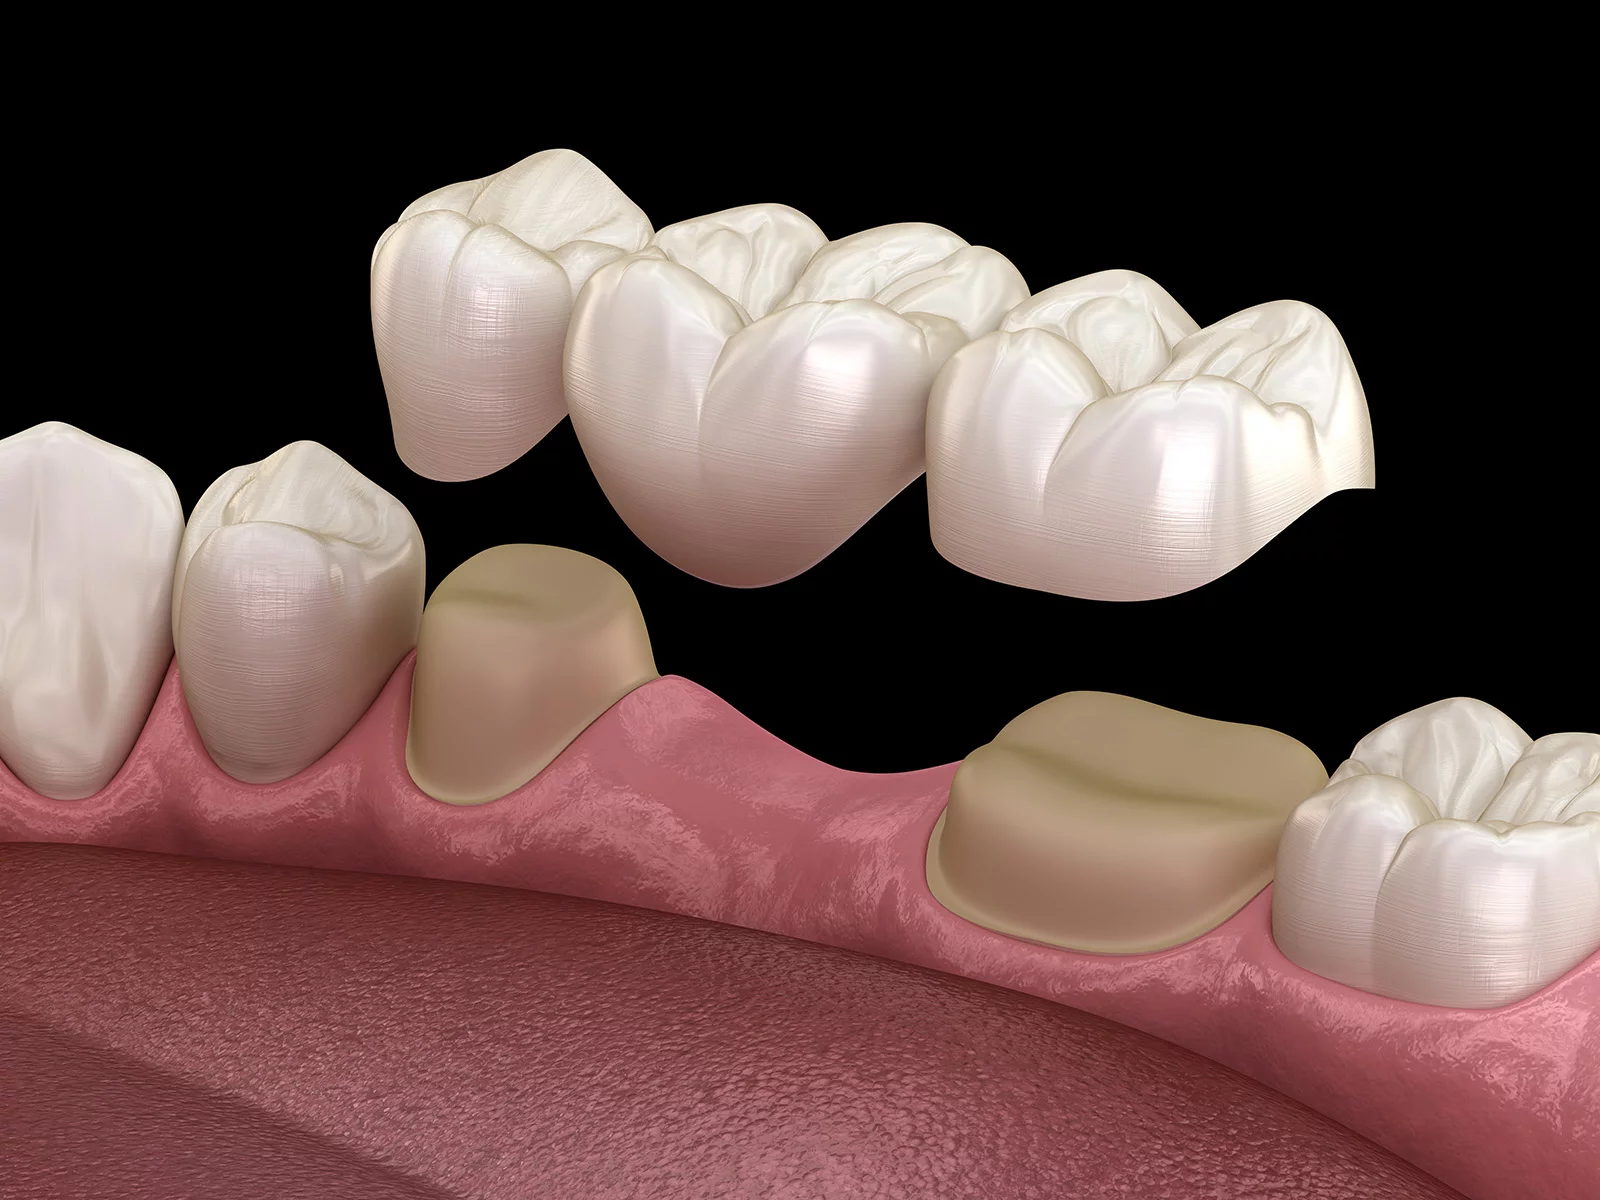

ブリッジ治療は、失った歯を補う方法として多くの方に選ばれている治療法です。ブリッジ治療では、失われた歯の両側にある健康な歯を支えにして、その間に人工の歯を設置します。しかし、この治療にはいくつかの欠点もあります。ここでは、その具体的な欠点について詳しく見ていきましょう。

ブリッジ治療では、人工歯を支える両隣の歯に大きな負担がかかります。この負担が原因で、支えとなる歯にダメージが蓄積し、最終的には抜歯が必要になることがあります。そのうえ、再びブリッジを選択すると、同様の負担がかかり続け、最終的には支える歯もなくなってしまうことがあります。その場合、総入れ歯を選ぶことが一般的です。